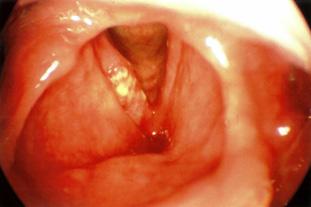

Figura 22. Colesteatoma adquirido primario de oreja izquierda. Pequeña erosión epitimpánica con colesteatoma. La piel que rodea la erosión está hiperémica y evertida.